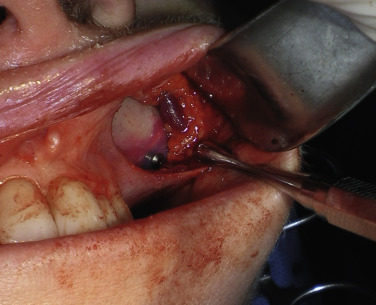

For small or medium submalar implants, minor zygomatic dissection is required, but for combined submalar and malar shell implants, more aggressive malar and zygomatic dissection is necessary. These larger implants also require more aggressive inferolateral dissection. It is not uncommon to encounter the origin of the masseteric tendon (or muscle) while dissecting in the area ( Fig. 7.15 ). There is no need to violate or dissect this tendon or muscle, because the silicone implant can safely lie over these soft tissue structures without a problem and frequently do with the larger-style implants. If adequate dissection is not performed over the masseteric tendon, it can create an obstruction and not allow the implant to sit passively. For smaller implants such as the medium submalar, the extended dissection over the masseteric tendon is usually unnecessary.